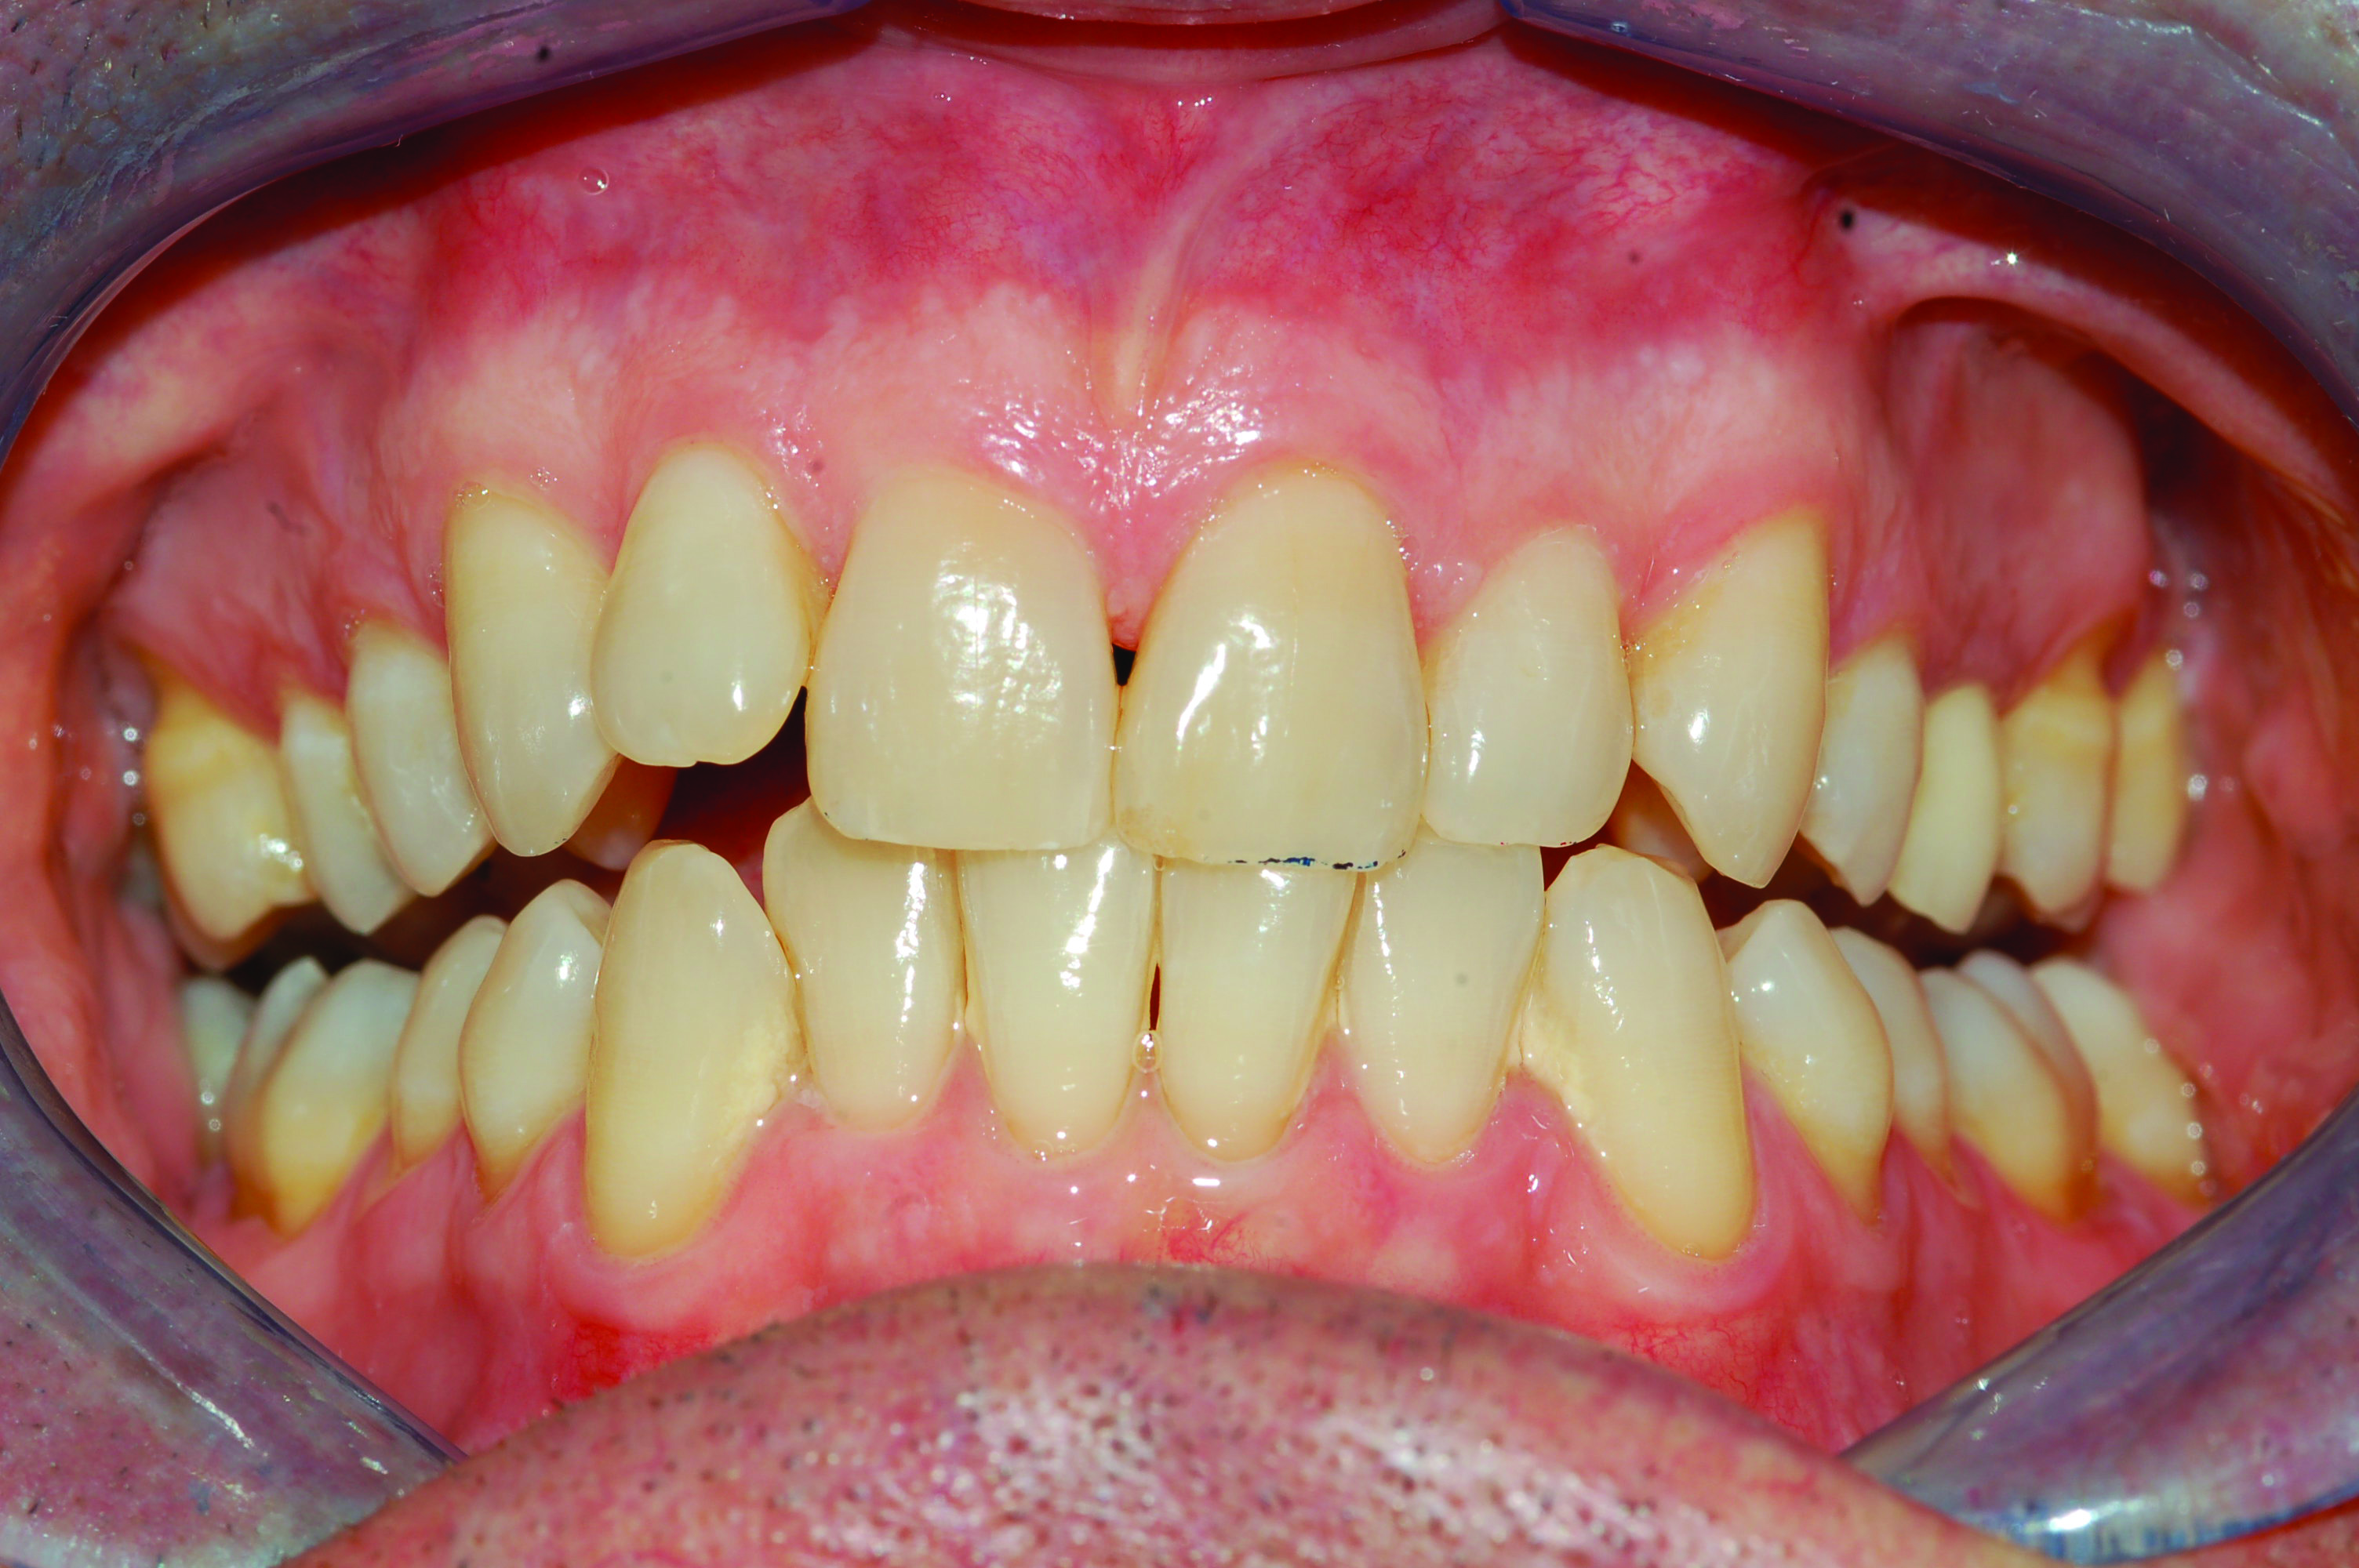

Fig 5. Development of dental side effects of MAD therapy. Photograph of female patient with teeth maximally intercuspated prior to treatment (AHI = 7.1 events/hr).

Figure 5

Fig 6. Photograph of teeth maximally intercuspated 1 year after patient began treatment with a MAD (Herbst appliance). With the jaw advanced 80% of maximum protrusion, the AHI was reduced to 1.4 events/hr. Compared to the pre-treatment occlusion (Figure 5), overbite and overjet had each decreased 2 mm.

Figure 6

In holding the jaw forward, MADs apply backward forces to the maxillary teeth and forward forces to the mandibular teeth in proportion to the amount of advancement. With time, these forces can produce changes in tooth or jaw position, resulting in changes in the dental occlusion.10,11 A decrease in overjet and overbite is most commonly observed (Figure 5 and Figure 6).